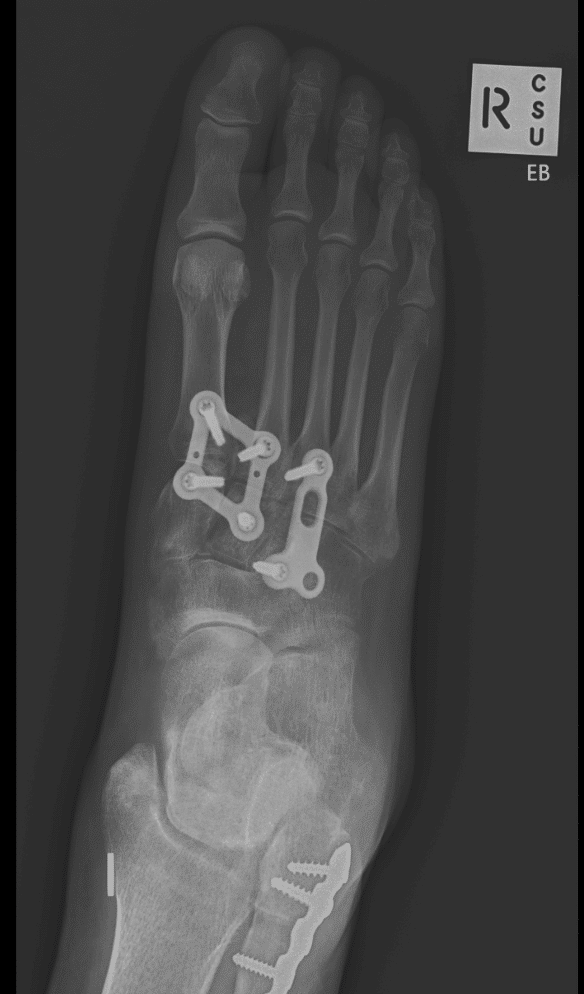

Specialised plates and implants allow for support of the healing ligament and generally can be later removed with minimal damage to the affected joints. Occasionally the injury will be so severe that the joints require fusion rather than stabilization and this will be discussed with you prior to managmement.

Surgery involves incisions on the top of the foot and mobilisation if the nerves and arteries supplying the toes. An area of numbness over the scar and distant to this is expected but will reduce with time. X-ray in the operating theatre is used to ensure the stabilisation of the affected joints and position of metal fixation which is designed so that it can stay in the foot for the long time it takes for this injury to heal.